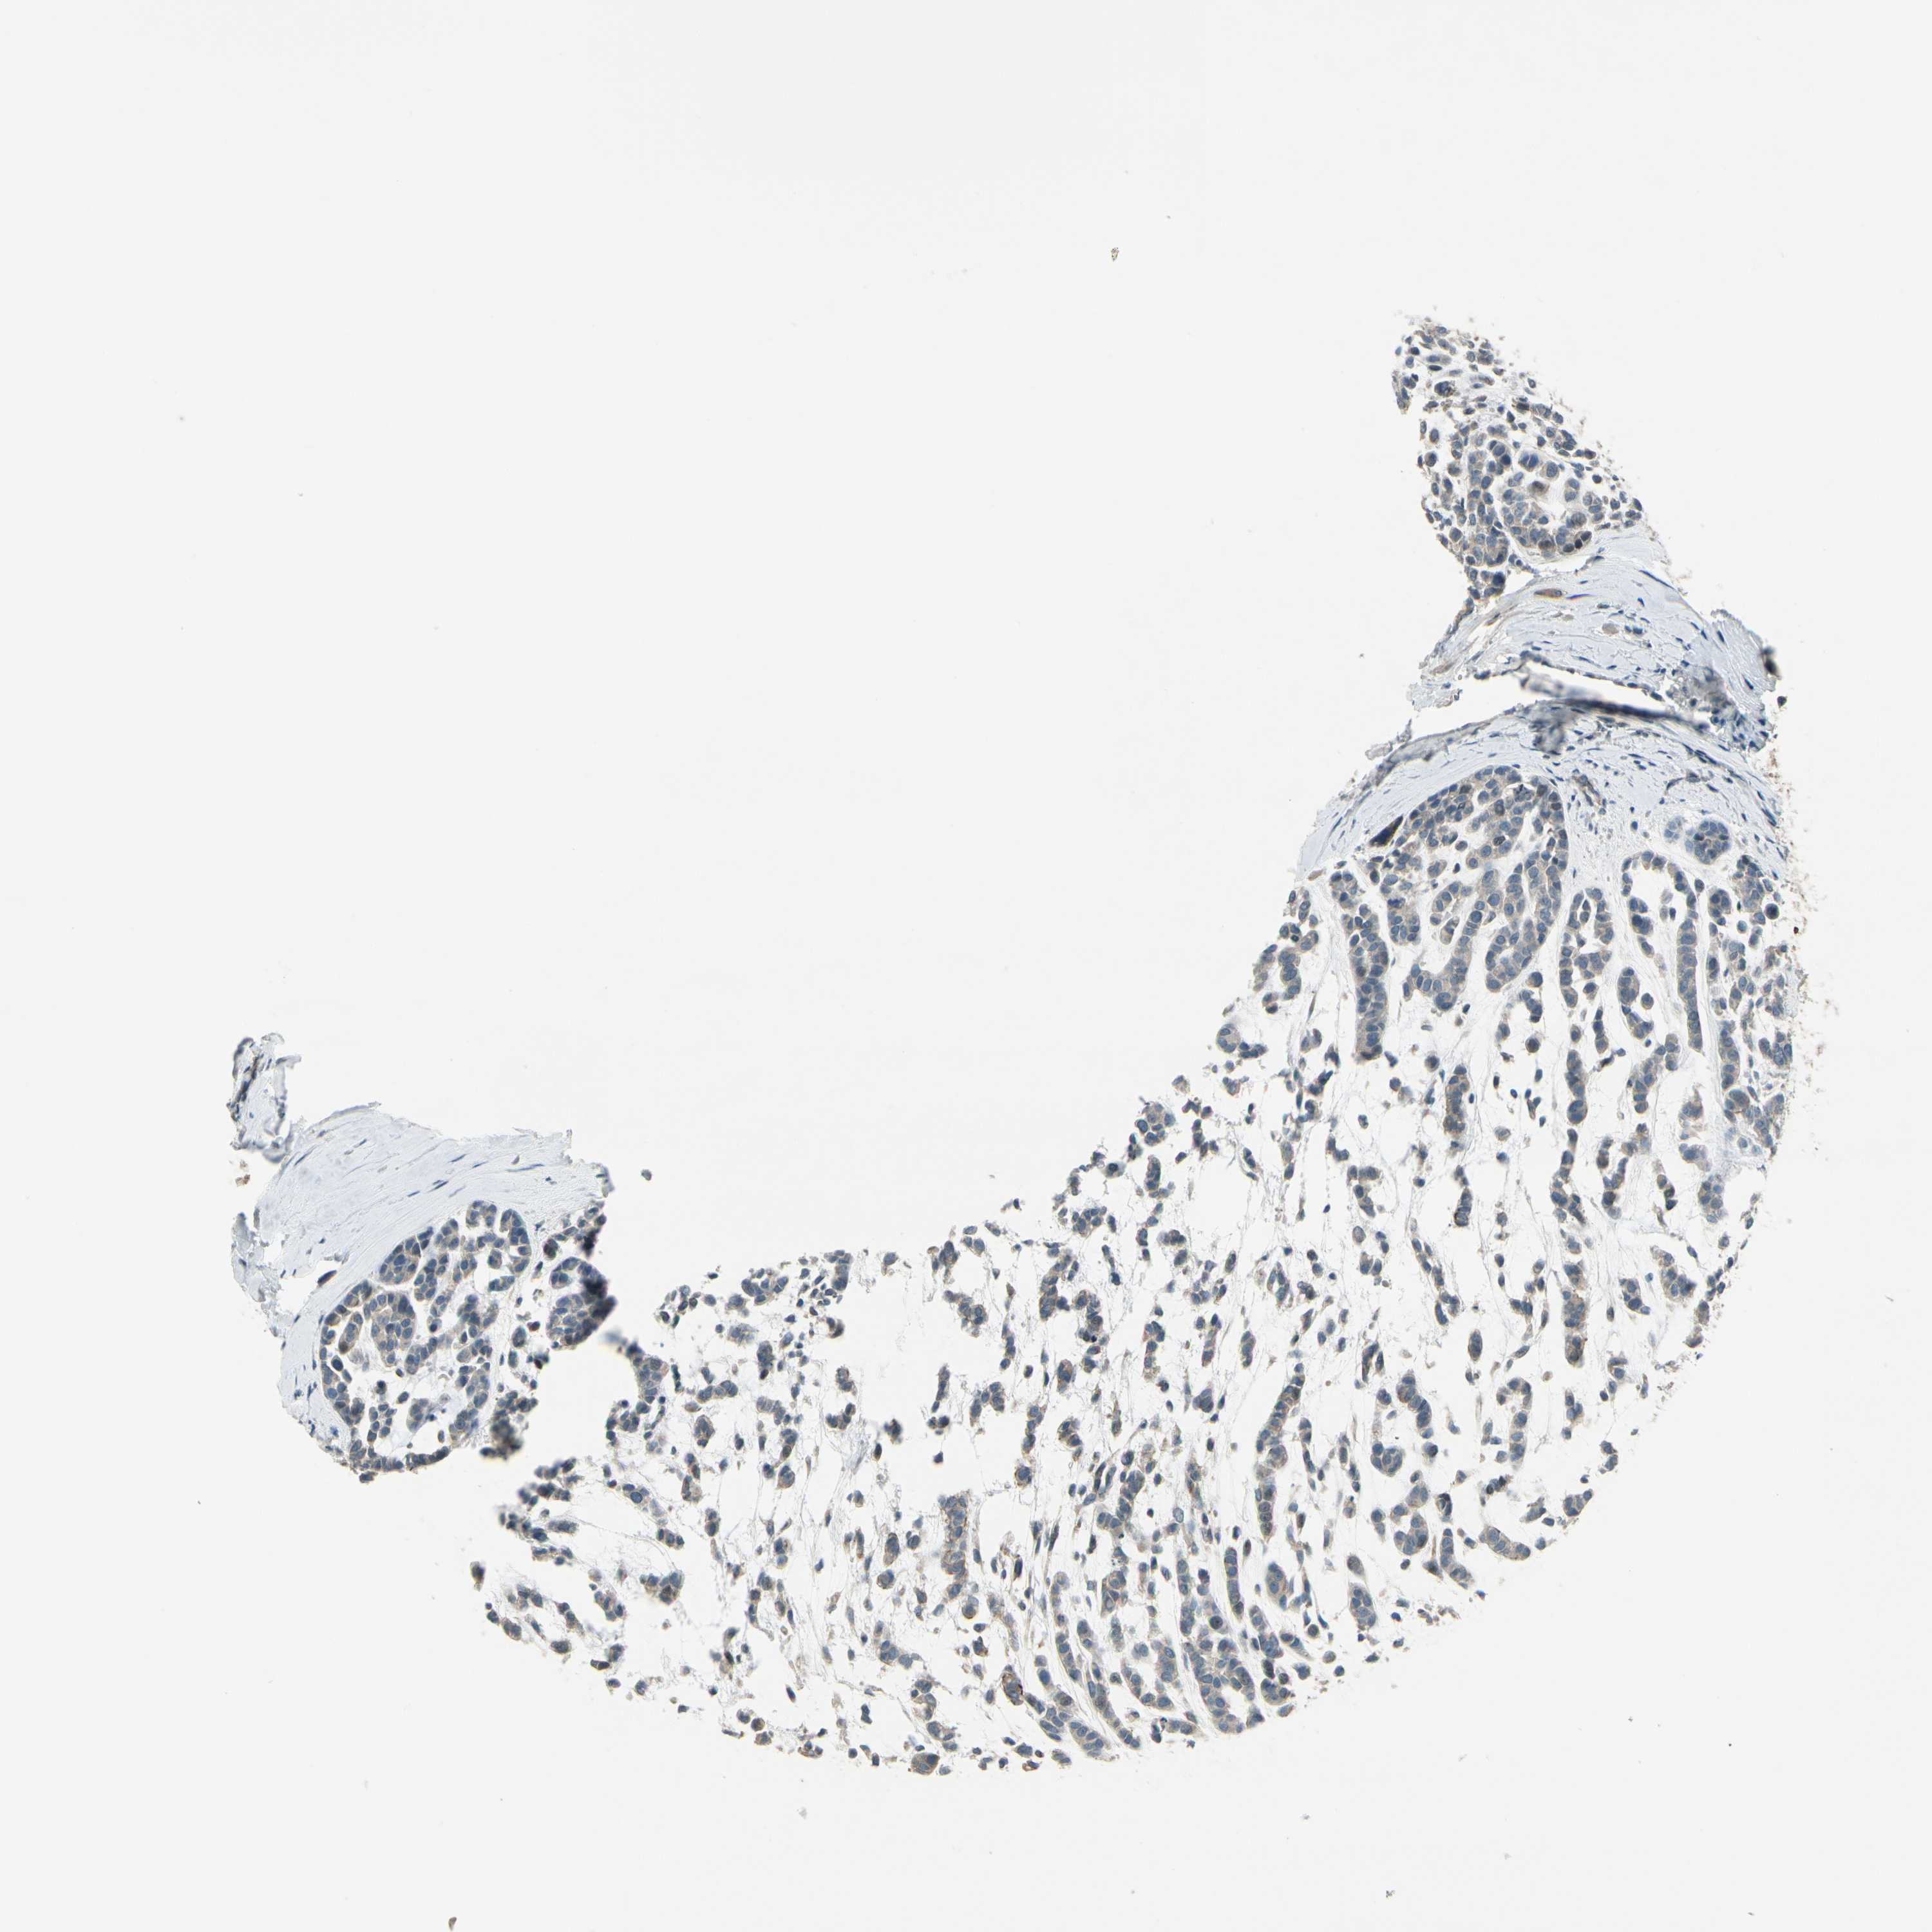

HEAD AND NECK CANCER - Protein expressioni

A mouse-over function shows sample information and annotation data. Click on an image to view it in a full screen mode. Samples can be filtered based on level of antibody staining by selecting one or several of the following categories: high, medium, low and not detected. The assay and annotation is described here.

Antibody stainingi

Antibody staining in the annotated cell types in the current human tissue is reported as not detected, low, medium, or high, based on conventional immunohistochemistry profiling in selected tissues. This score is based on the combination of the staining intensity and fraction of stained cells.

Each image is clickable and will lead to virtual microscopy that enables deeper exploration of all samples and also displays staining intensity scores, fraction scores and subcellular localization as well as patient and tissue information for each sample.

Antibody HPA008233

Staining

High

Medium

Low

Not detected

Intensity

Strong

Moderate

Weak

Negative

Quantity

>75%

75%-25%

<25%

None

Location

Nuclear

Cytoplasmic/membranous

Cytoplasmic/membranous,nuclear

Squamous cell carcinoma, NOS

Squamous cell carcinoma, metastatic, NOS

Adenocarcinoma, NOS

Adenoma, NOS